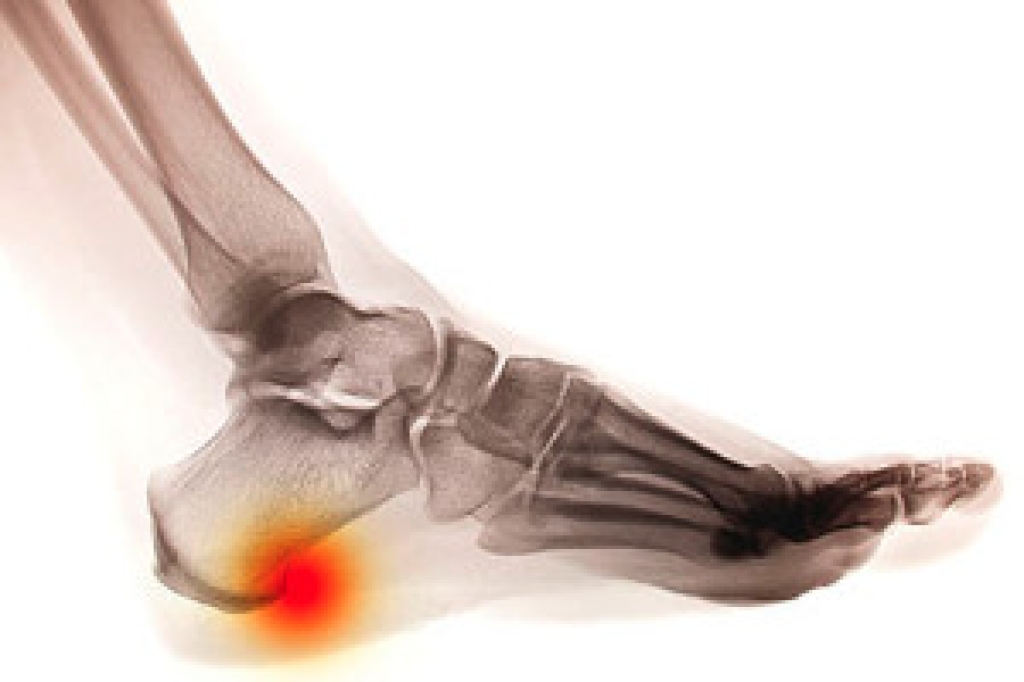

As you age, your feet require extra attention and care to maintain mobility and overall well-being. Proper foot care is essential for seniors to prevent common issues such as foot pain, infections, and injuries. Regular inspection of the feet is vital, and this includes checking for cuts, sores, or signs of infection, especially for those with diabetes or circulatory issues. Keeping the feet clean and dry, including thorough drying between the toes, helps prevent fungal infections like athlete's foot. Seniors should wear comfortable, properly fitting shoes with adequate support and cushioning to reduce pressure and friction on the feet. Regular foot exercises and stretches can improve circulation, flexibility, and strength, enhancing balance and reducing the risk of falls. Additionally, maintaining a healthy lifestyle with proper nutrition and hydration supports overall foot health. If you are a senior experiencing foot pain, it is strongly suggested that routine appointments are scheduled with a podiatrist who can provide you with relief options.

As we age we start to notice many changes in our body, but the elder population may not notice them right away. Medical conditions may prevent the elderly to take notice of their foot health right away. Poor vision is a lead contributor to not taking action for the elderly.

Diabetes and poor circulation can cause general loss of sensitivity over the years, turning a simple cut into a serious issue.